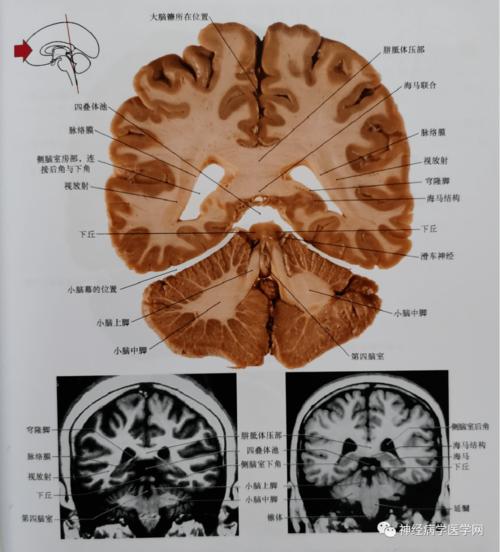

切面,见图3-2-22;②透明隔和尾状核切面,见图3-2-23;③丘脑冠状切面

通过松果体,丘脑枕的尾部,上丘,脑干被盖,小脑中脚平面的冠状位